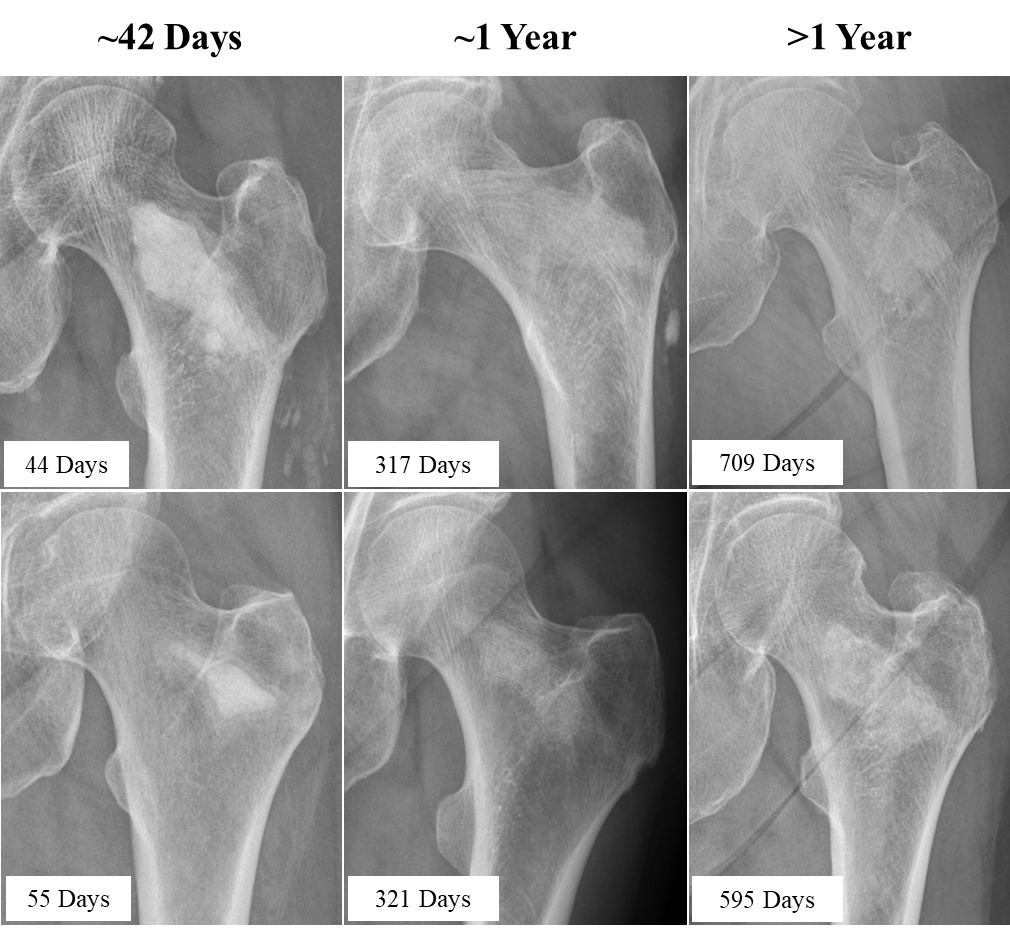

All post-operative radiographs were assessed by the PI for resorption of the implant material and its replacement with bone. Resorption was assessed in 25% increments, with 0% resorption defined as 100% residual implant material on the initial post-operative X-ray, and complete (100%) resorption defined as 0% residual implant material remaining in the initially filled enhancement site. The PI also recorded whether or not resorbed implant material was successfully replaced with new bone, with new bone defined as having radiodensity at least as great as the surrounding trabecular bone with evidence of bone remodeling.

The PI evaluated implant resorption and regional new bone formation on post-LOEP radiographs that were available for 26/50 treated hips; these radiographs were obtained an average of 311 ± 280 days after LOEP (range, 23 – 842 days). Radiographs from six representative patients at three different post-operative time points are highlighted in Figure 2. The mean area of high radiodensity associated with the residual material was 29% ± 40% compared to the post-injection fluoroscopic images, with a median value of 0% (interquartile range 0%, 75%) (Supplemental Table S6). Twenty-five of 26 hips (96.2%) showed radiodensity consistent with new local bone formation, and the single hip film that did not was obtained just 23 days post-LOEP.

Marked post-LOEP increases in femoral neck and total hip BMD were observed among the substantial subset of participants with pre- and post-LOEP DXAs, with the latter scans obtained an average of 397 days post-LOEP. Radiographic evaluation indicated substantial implant resorption after a mean follow-up of 311 days, at which time 96% of all treated hips exhibited radiodensity at the LOEP site consistent with that of normal trabecular bone. These findings corroborate previous evidence of new bone formation and substantial long-term (5-7-year) BMD gains in AGN1 LOEP-treated hips of women with postmenopausal osteoporosis (Howe et al. 2020). VAS Pain Assessment scores and Forgotten Joint Scores improved from pre-LOEP to post-LOEP assessments, with both PRO measures improving to degrees that are considered clinically significant (Bird and Dickson 2001; Robinson et al. 2021). These PRO findings should be interpreted with caution due to the open-label nature of the study.